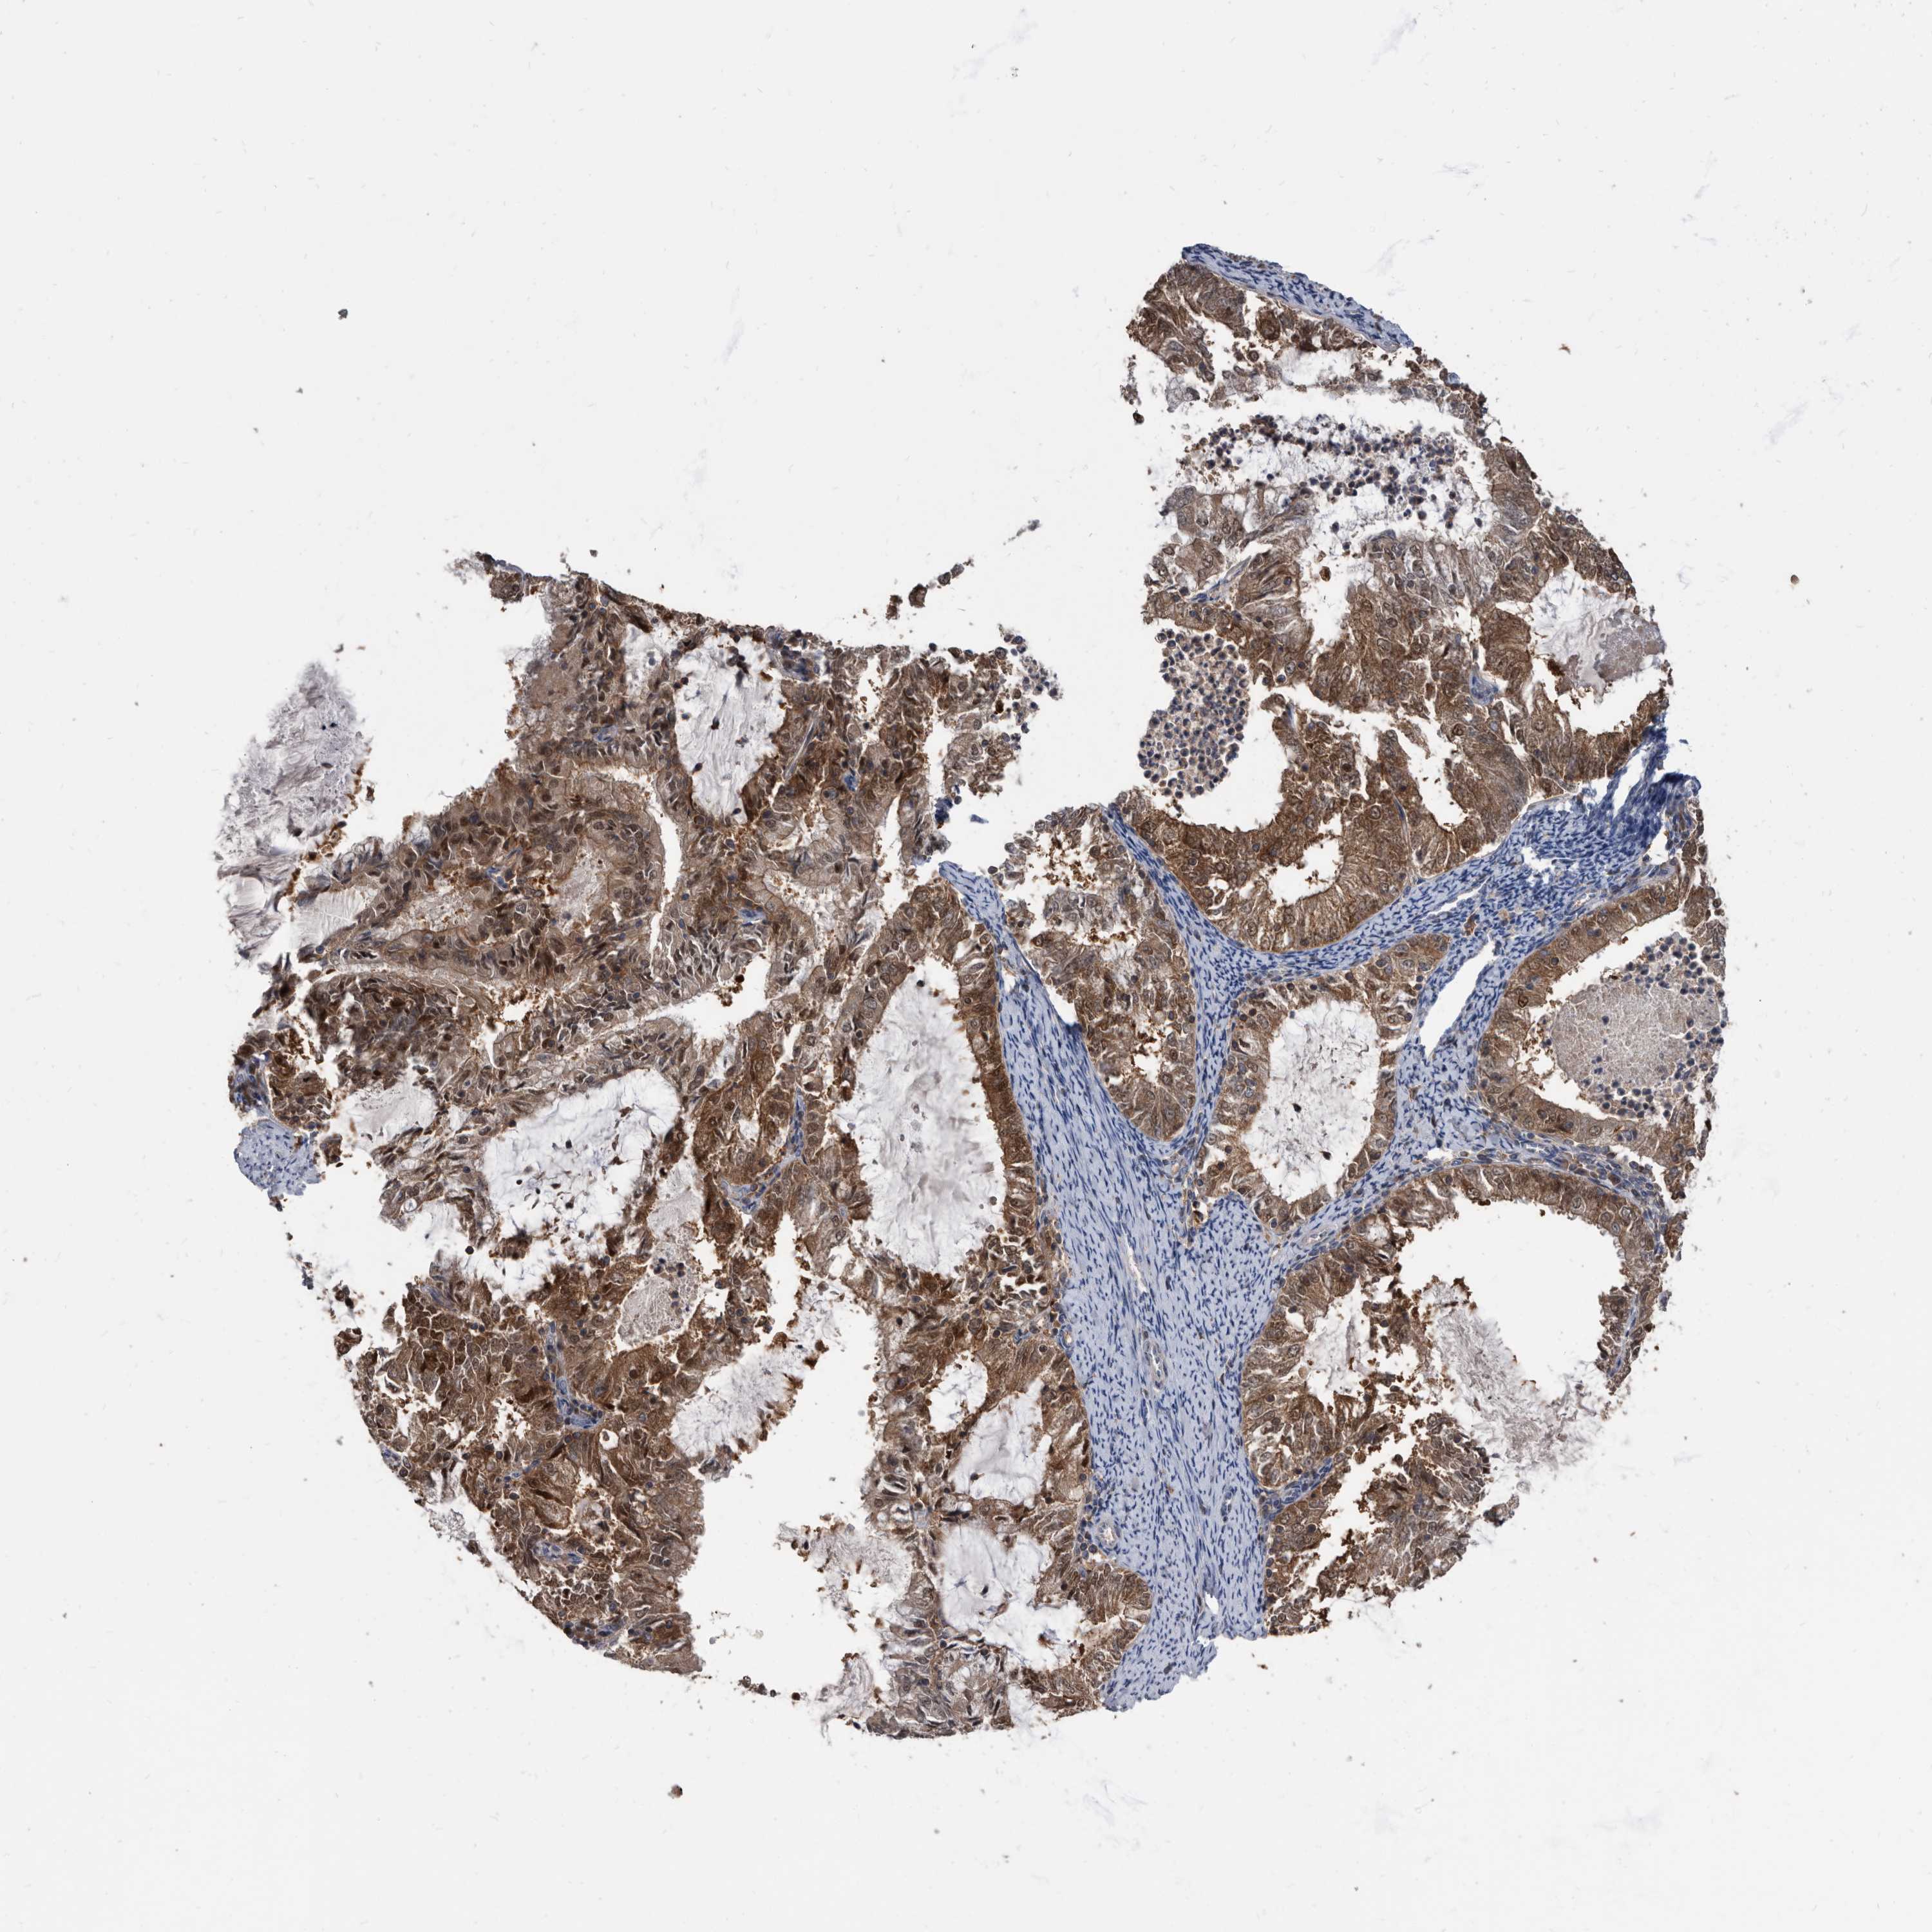

ENDOMETRIAL CANCER - Protein expressioni

A mouse-over function shows sample information and annotation data. Click on an image to view it in a full screen mode. Samples can be filtered based on level of antibody staining by selecting one or several of the following categories: high, medium, low and not detected. The assay and annotation is described here.

Note that samples used for immunohistochemistry by the Human Protein Atlas do not correspond to samples in the TCGA dataset.

Antibody stainingi

Antibody staining in the annotated cell types in the current human tissue is reported as not detected, low, medium, or high, based on conventional immunohistochemistry profiling in selected tissues. This score is based on the combination of the staining intensity and fraction of stained cells.

Each image is clickable and will lead to virtual microscopy that enables deeper exploration of all samples and also displays staining intensity scores, fraction scores and subcellular localization as well as patient and tissue information for each sample.

Antibody HPA029700

Antibody HPA029701

Antibody HPA029702

Antibody HPA029703

Staining

High

Medium

Low

Not detected

Intensity

Strong

Moderate

Weak

Negative

Quantity

>75%

75%-25%

<25%

None

Location

Nuclear

Cytoplasmic/membranous

Cytoplasmic/membranous,nuclear

Adenocarcinoma, NOS

Adenocarcinoma, metastatic, NOS